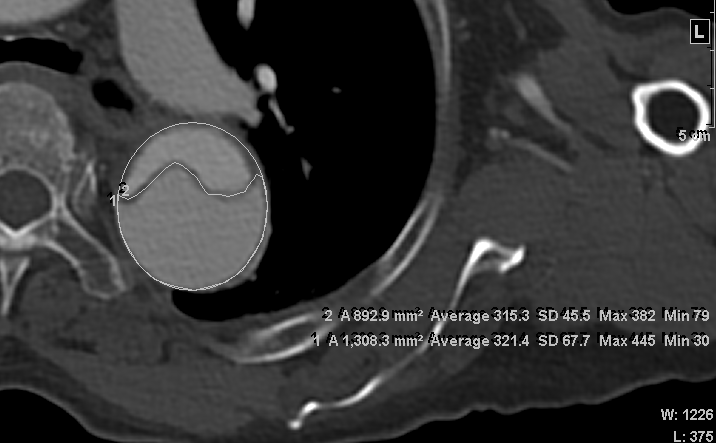

Methods : We analyzed 309 non-syndromic acute type I aortic dissection patients, who were treated with a repair to the proximal aorta between 1994 and 2017. From 230 patients who did not show completely thrombosed false lumen on post-operative computed tomography (CT), MFLA ratio (MFLA/aortic area) on descending thoracic or abdominal aorta was measured with post-operative CT. The patients were divided into 3 groups according to the quartile range of MFLA ratio: low (<0.62, n=57), intermedius (0.62-0.81, n=116), and high (≥0.82, n=57) MFLA group.

Results : The 10-year freedom from aortic reintervention rate was significantly lower in high MFLA group (37.4±7.6%) compared with low (97.9±2.1%, p<0.01) and intermedius (91.0±3.4%, p<0.01) MFLA group. The aortic expansion rate was significantly higher in high MFLA group (11.5±21.2mm/year) compared with low (1.1±7.6mm/year, p<0.01) and intermedius (3.6±7.6mm/year, p=0.02) MFLA group. The 10-year freedom from significant aortic expansion rate was significantly lower in high MFLA group (33.5±7.9%) compared with low (97.6±2.4%, p<0.01) and intermedius (73.9±6.6%, p<0.01) MFLA group. The multivariate analysis showed that a high MFLA was an independent risk factor for aorta reintervention (HR=5.84, 95% CI=2.35-14.50, p<0.01) and significant aortic expansion (HR=2.22, 95% CI=1.15-4.30. p=0.02).

Conclusion : A high MFLA ratio on descending thoracic or abdominal aorta after acute type I aortic dissection repair was associated with increased the risk of late aortic reintervention and distal aortic dilatation.